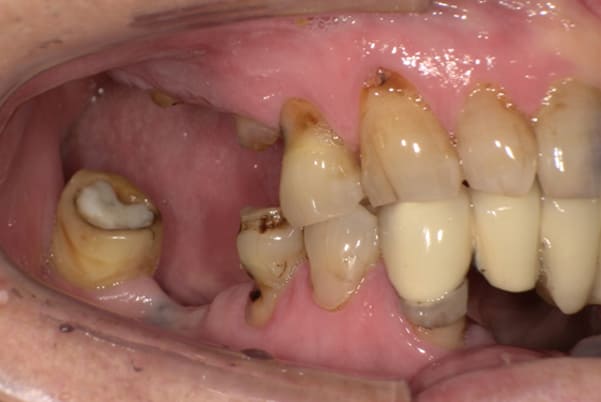

症例レポート[CASE.02]

入れ歯がカパカパして痛い、

歯がぐらぐらする

- 男性(60代)

- 入れ歯がカパカパする、歯がぐらぐらして痛い、食いしばれない

- 上顎精密総金属床総入れ歯

- 下顎精密金属床部分入れ歯

上の前歯が重度歯周病により動揺し、残せない状態のため、入れ歯も動揺がありました。

ご自身の歯に負担の少ないバネ、また見た目も改善

バネをかける歯は繋げることで強度を増し、歯への負担を軽減し、歯の寿命を長くする設計へ。

バネがかかる歯の被せ物は、歯への負担を減らし、入れ歯が動きにくいようになる形態をあらかじめ付与することで、より入れ歯の機能が高まります。

治療を行う際、被せ物や入れ歯は、別々に考えるのではなく、一口腔単位としてお口全体のことを考え最良の治療計画を立てることが歯の寿命、機能効果を向上させるため、専門医としてこのことは常に心掛けて治療を行っています。

治療前は上下奥歯の入れ歯が削れていることで、かみ合わせが低くなり唇もつむった状態でした。

かみ合わせを適切な高さに戻したことで、本来の自然な口元へ。